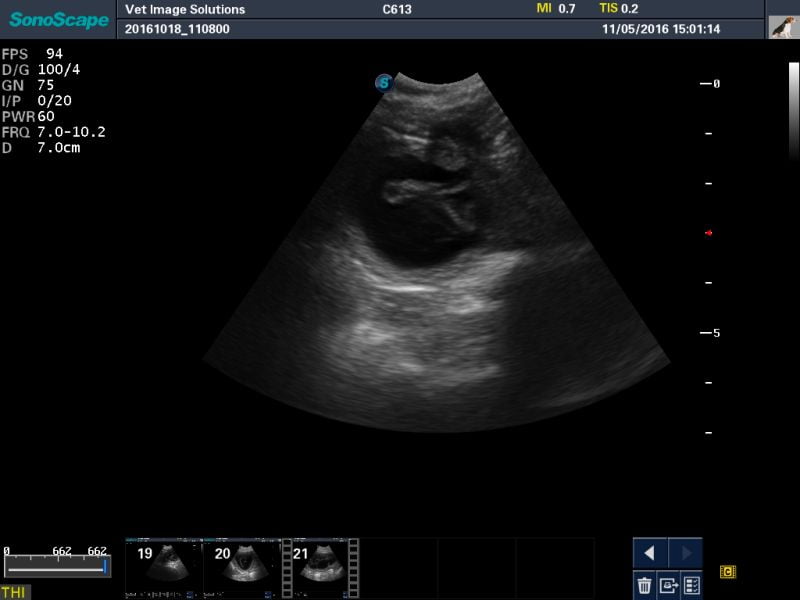

It was possible to scan at the highest frequency (7-10MHz) on Bella, because she is so tiny! This meant that we could obtain a high level of detail, even at